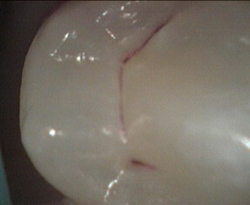

side groove decay side groove decay restored